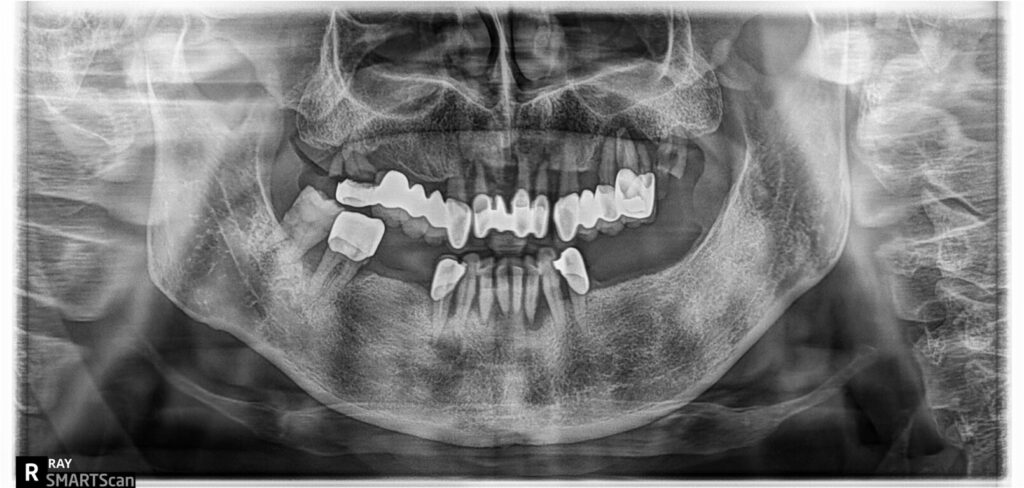

잇몸질환(치주염)이 심한 전체임플란트 사례의

치료전 엑스레이

전체임플란트 치료전후

파노라마 비교

치료전 파노라마 상에서 심하게 치조골이 파괴된 자리인 왼쪽 위 작은어금니 부분은 임플란트를 심지 않고 연결하는 방식으로 처리했구요. 위쪽 어금니부분에는 간단한 상악동 이식술을 시행했습니다. 아래 오른쪽 송곳니부분에도 뻐이식이 진행되었어요. 이렇게 발치와 임플란트식립, 뼈이식이 모두 하루에 진행이 됩니다. 저는(이한나원장) 수천명의 전체임플란트 치료 사례를 시술했으며, 손이 빠르고 정확해서 수술시간이 빠릅니다. 수술시간이 빠르면 경과도 좋고 환자도 덜 힘듭니다.